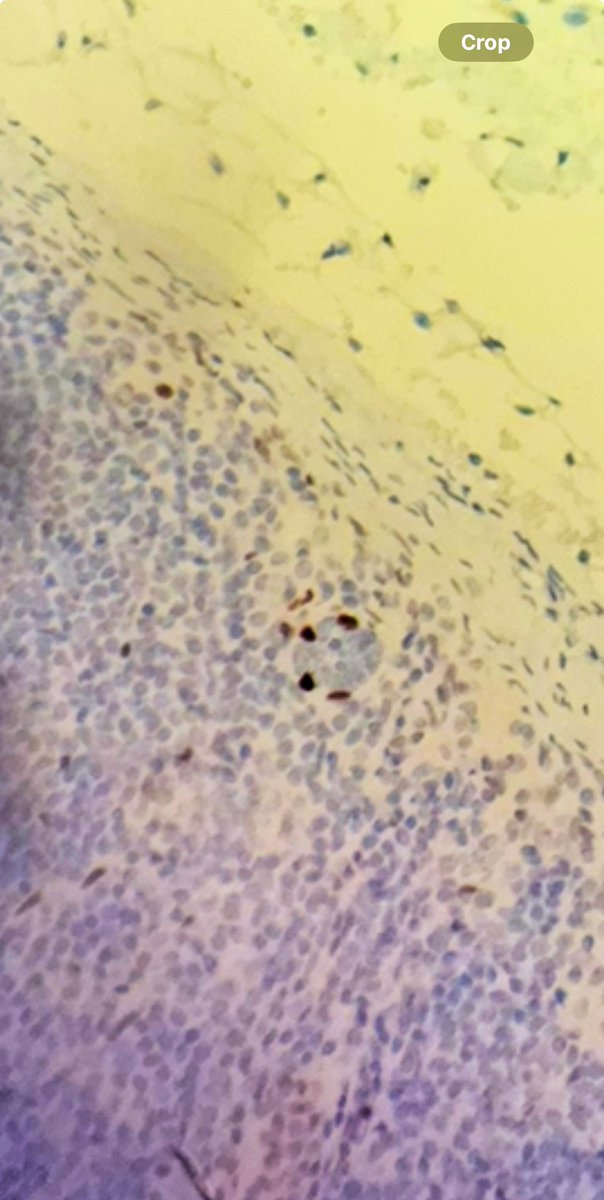

At a #USCAP2025 poster session today, @lorrainecolonMD, Assistant Professor of #Pathology Yale School of Medicine, presented on breast pathology. @The USCAP